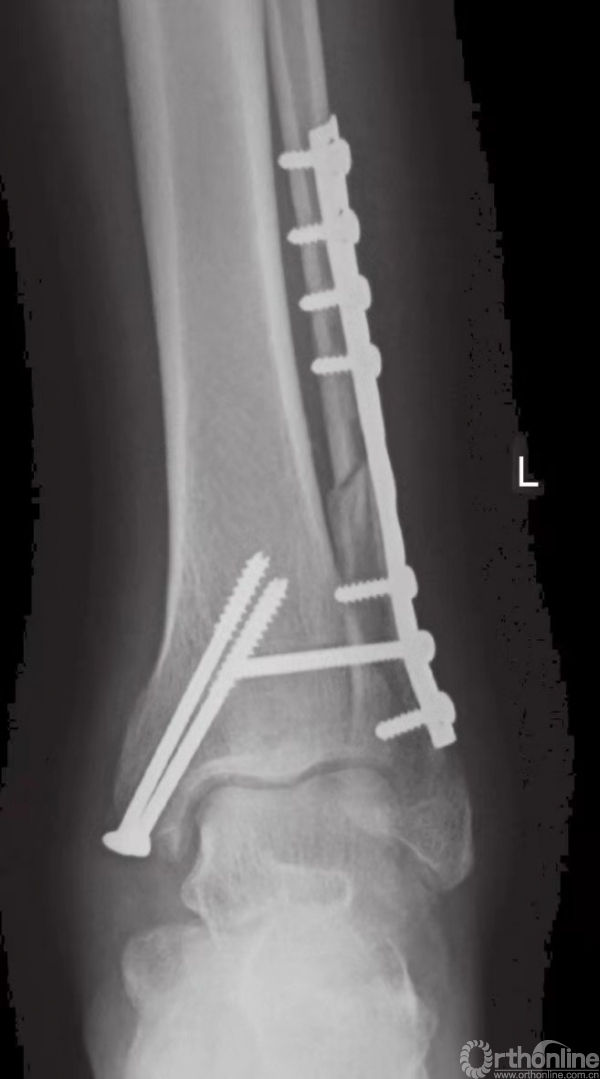

外踝固定技术

腓骨远端为皮下骨骼,因此应避免以腓骨远端为中心直接切开成口。一般在腓骨远端的后外侧表面切口(图2),这样就避免了伤口张开或裂开时接骨板暴露。如果因粉碎性骨折和Pilon骨折而要在踝关节前方开口,上述切口也可与该切口保持足够的距离。

清理骨折末端软组织后,借助小复位钳将骨折片复位(图4)。解剖复位和腓骨长度的保持,尤为重要。除了腓骨的长度之外,也应检查旋转的方向。腓骨的短斜形骨折可用一枚拉力螺钉和一块中和接骨板加以固定(图5~8)。

长螺旋形骨折可用两枚拉力螺钉和一块中和接骨板加以固定。骨折线的两侧最少须四皮质固定。较小的1/3或半形管状接骨板通常用于固定腓骨。3.5mm的动力性加压接骨板也被用于体型较大的患者。近期,用于腓骨固定的特制接骨板也被研发出来。

当发生腓骨粉碎时,使用桥形接骨板,从而能绕过碎骨,皮质固定也可在骨折区域上下完成。在用螺钉固定前,应预先描出接骨板的轮廓。有时,如果在很低的位置发生横行骨折,可在踝部用4mm的张力性钢丝带加以固定。术中进行影像学检查,可以极为有效地避免远端的螺钉将关节刺穿(图9)。